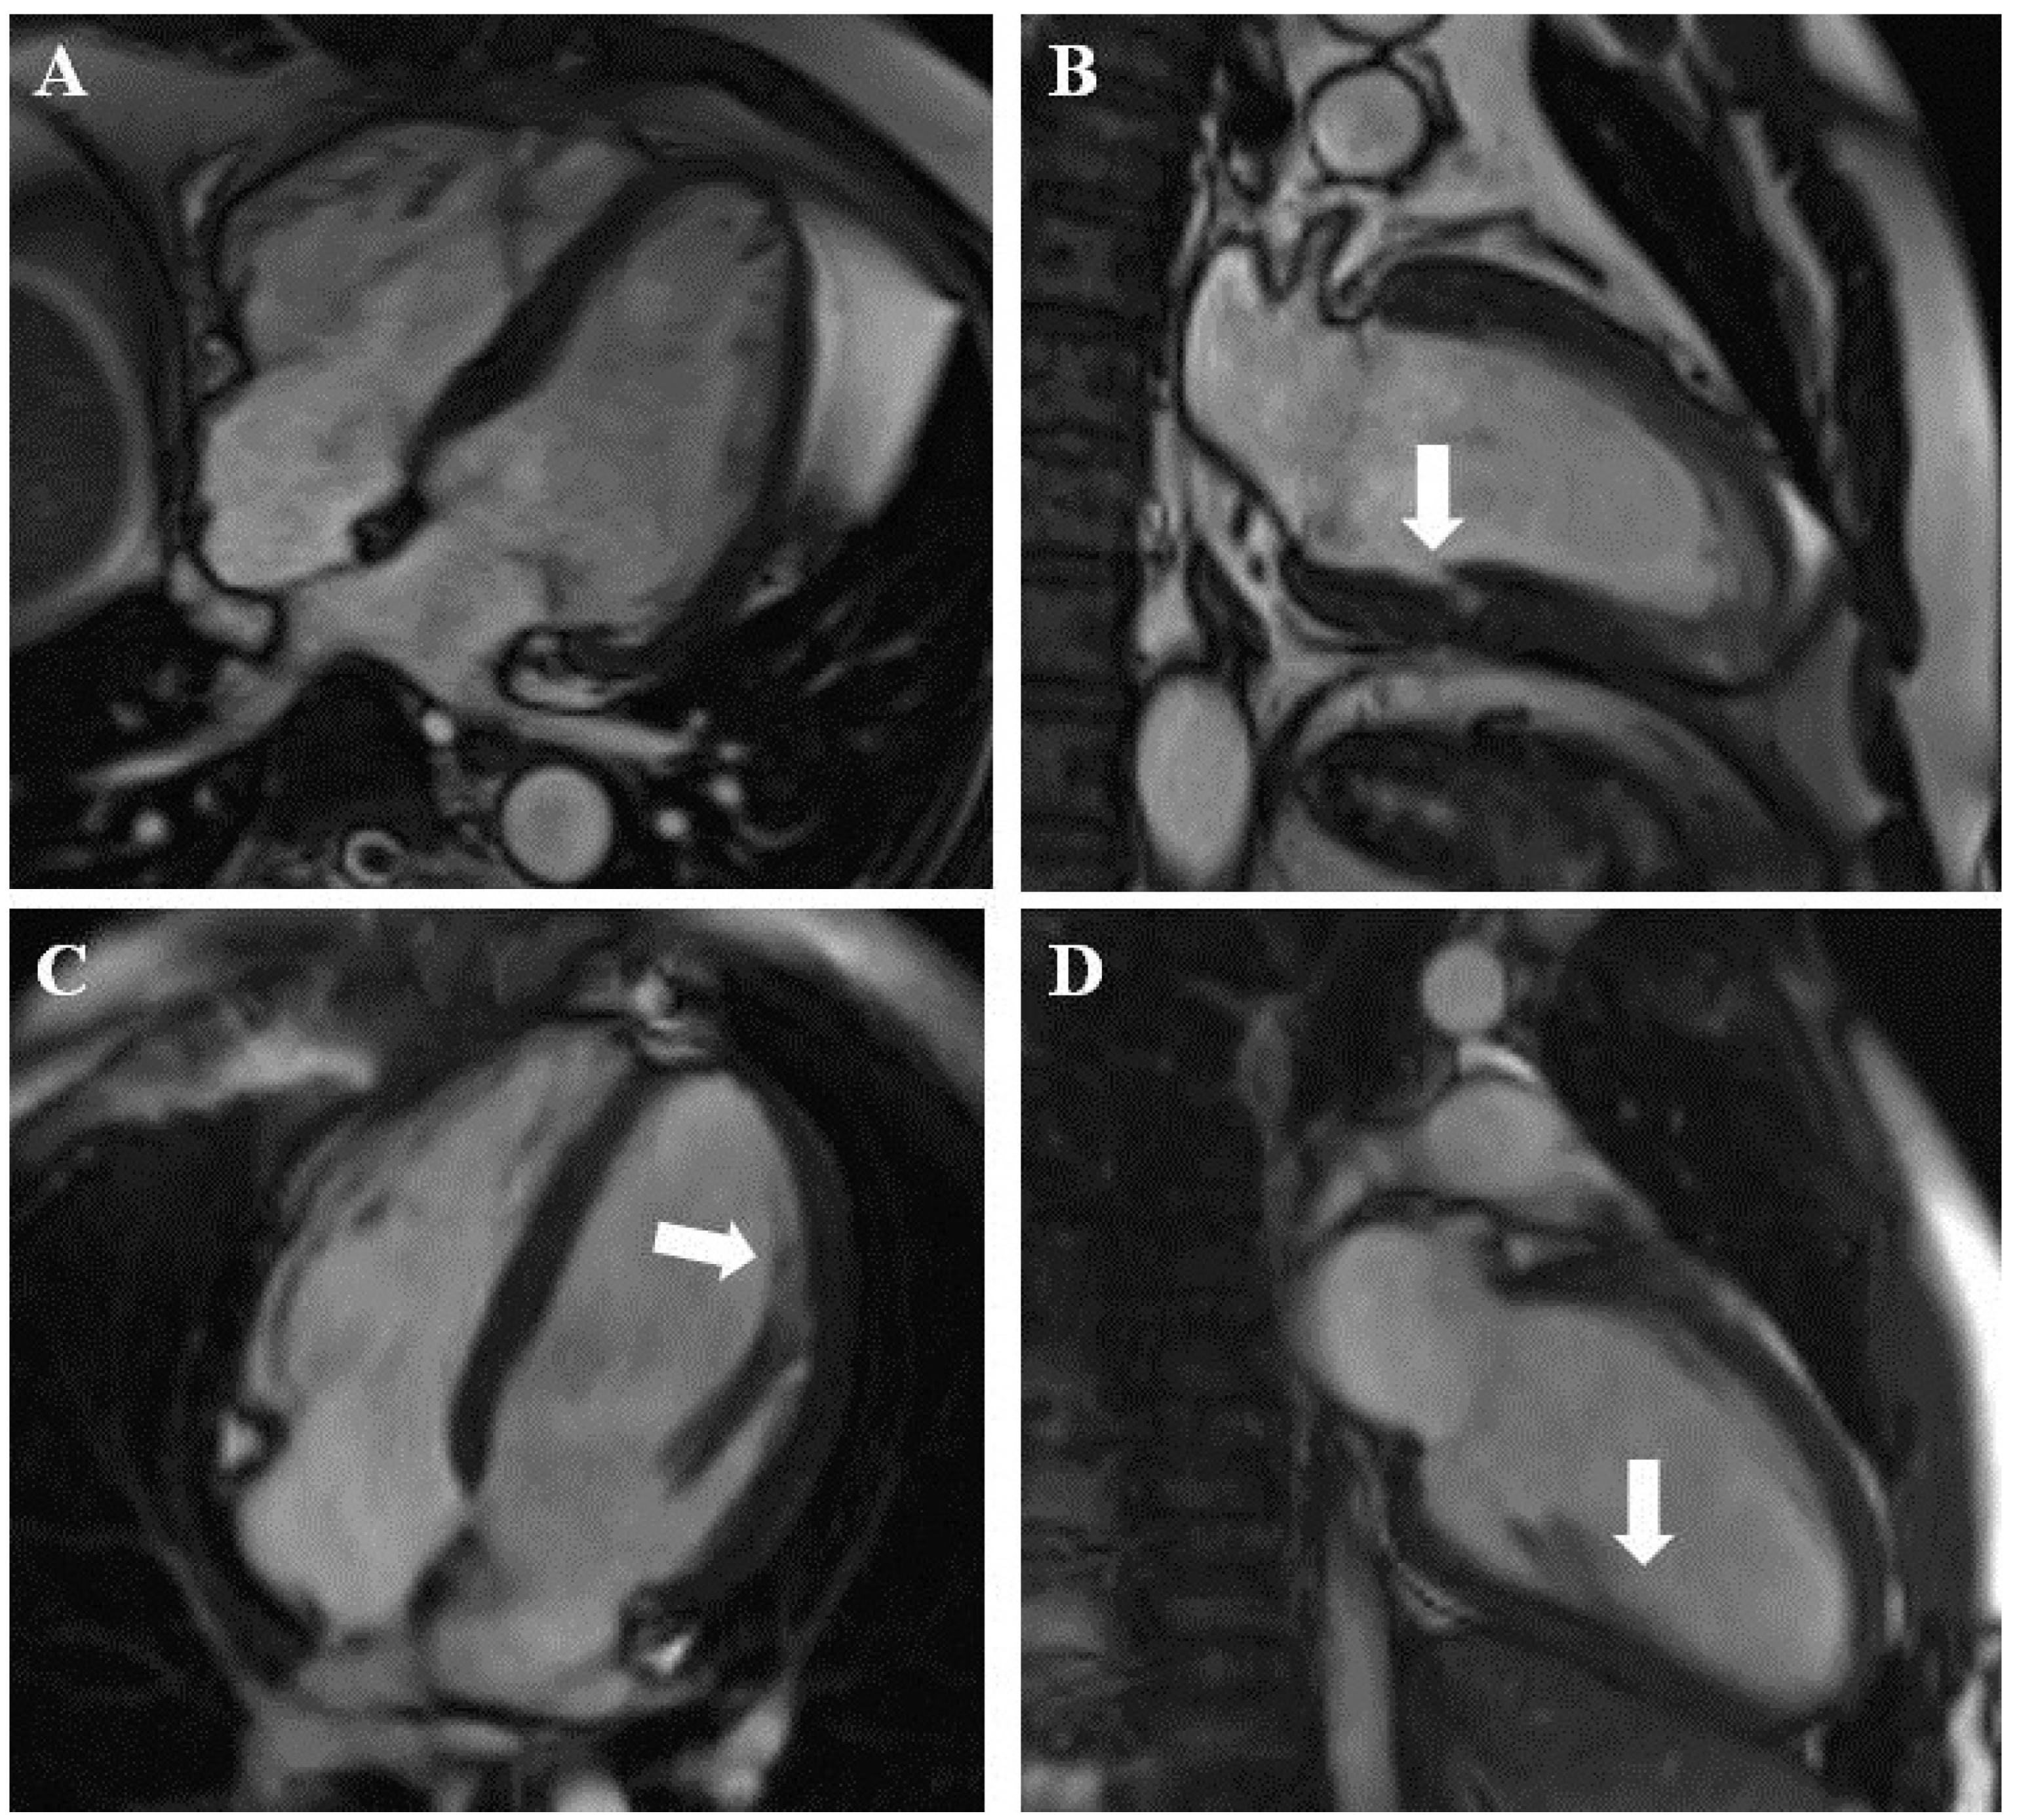

Impact of Cardiac Magnetic Resonance on the Diagnosis of Left Ventricular Noncompaction—A 15-Year Experience

3.2. CMR Diagnosis